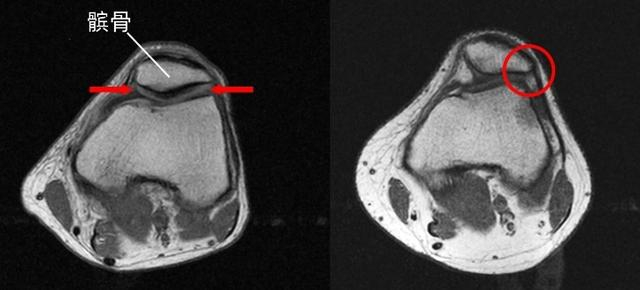

髌股关节由髌骨后表面和股骨髁间窝构成,其稳定性主要依赖于髌骨与股骨髁间窝的契合度。当人体进行屈膝、伸膝等动作时,髌骨会在股骨髁间窝中上下滑动。谢医师解释说,PFPS的发病原因可能包括膝关节的过度使用、髌骨的异常轨迹等。例如,频繁参与跑步、跳跃等运动会对膝关节产生重复性压力,而髋、膝周围肌肉力量不平衡和下肢力线不正常则可能导致髌骨轨迹异常,增加髌股关节的压力,从而损伤膝关节软组织。